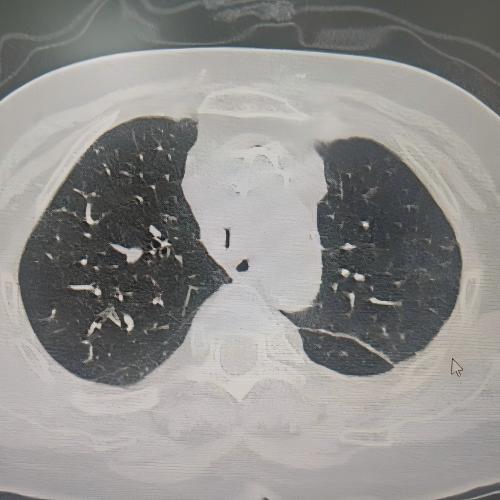

患者为75岁女性,因“反复咳嗽咳痰、气促10余年,加重3月”,于3月3日入住湘雅三医院呼吸与危重症医学科。入院时患者呼吸困难症状严重,CT检查提示气道存在严重狭窄,随时面临窒息风险。经管床医生杨红辉副主任医师评估,患者气管狭窄情况复杂:最狭窄处管腔直径仅剩1-3mm,科室最细的4.0mm支气管镜也无法通过;狭窄位置极低,下缘距隆突仅1.6cm,意味着无法通过气管切开绕过病灶;狭窄处周围组织的CT值高达60-70Hu且无强化,因而直接植入支架存在无法撑开或加重堵塞的风险;同时,患者无法耐受全身麻醉,仅能采用利多卡因进行表面麻醉,操作难度较大。

方案确定后,ICU团队为何智辉、邢伟、邓龙天为患者建立体外生命通道;呼吸介入团队孟婕、杨红辉、刘建明、邹丽君、贺一峻等通过球囊对狭窄部位进行预扩张,随后在距隆突仅1.6cm的低位气道精准植入支架。支架贴合良好,气道顺利开通,全程操作约1.5小时。患者当晚撤离ECMO,次日从ICU转回普通病房。后续肺泡灌洗液检测显示,患者大气道狭窄的原因为气管结核导致的瘢痕性狭窄。